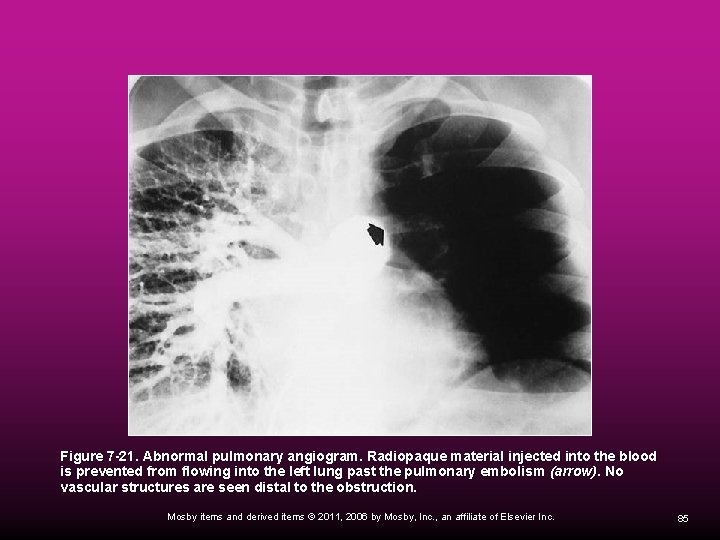

Pulmonary Angiography Pulmonary angiography is useful in identifying pulmonary emboli or arteriovenous malformation. It involves the injection of a radiopaque contrast medium through a catheter that has been passed through the right side of the heart and into the pulmonary artery. Mosby items and derived items © 2011, 2006 by Mosby, Inc. , an affiliate of Elsevier Inc. 84

Figure 7 -21. Abnormal pulmonary angiogram. Radiopaque material injected into the blood is prevented from flowing into the left lung past the pulmonary embolism (arrow). No vascular structures are seen distal to the obstruction. Mosby items and derived items © 2011, 2006 by Mosby, Inc. , an affiliate of Elsevier Inc. 85